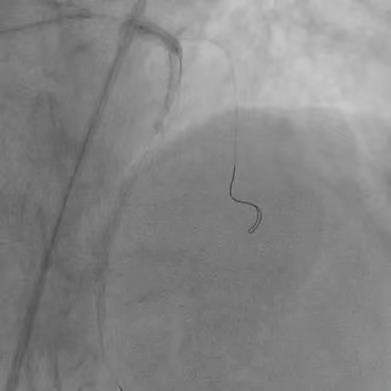

患者74岁,10年前因胸痛诊断为冠心病,在外院放过支架,但当时医生即明确告知家属,血管最严重的“总开关”左主干的地方钙化分叉,处理起来太危险,只是把难度相对不高的血管放了支架。近年来患者间断胸闷、胸痛,伴有心衰下肢肿胀,辗转来我院。冠脉CT显示冠脉严重钙化,因此安排冠脉造影检查。 ![]() ![]() 术前CTA提示左右冠支架术后且左主干重度钙化 (主干没有支架) 冠脉造影